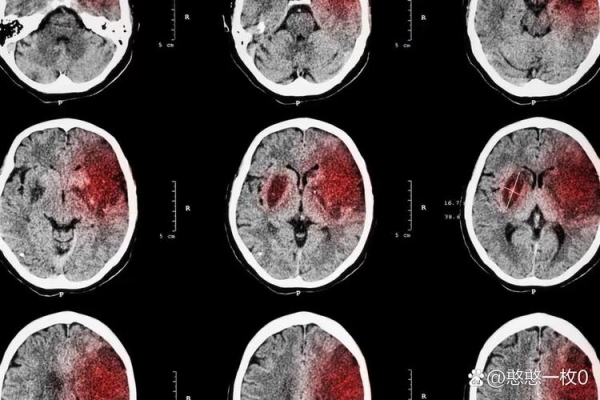

睡前出现这 5 个症状,当心是脑梗!

你睡觉前,身体会出现异常吗?有5个"异常"表现或许是脑梗预警信号!

1.头晕头痛突然加重,看东西天旋地转

如果在睡前准备躺下时,突然觉得头比平时疼好几倍,闭着眼睛都觉得房子在转,甚至站不稳,这可能提示你的脑组织已经出现缺血的情况了,血管可能已经开始痉挛。如果这时候头晕还伴随着恶心的症状,需要及时测量血压,必要时务必去医院就医。